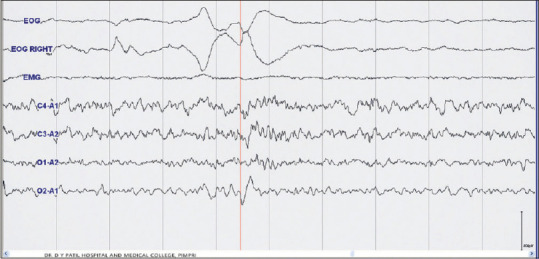

Figure 1.

Sleep laboratory recording of the patient showed no abnormalities